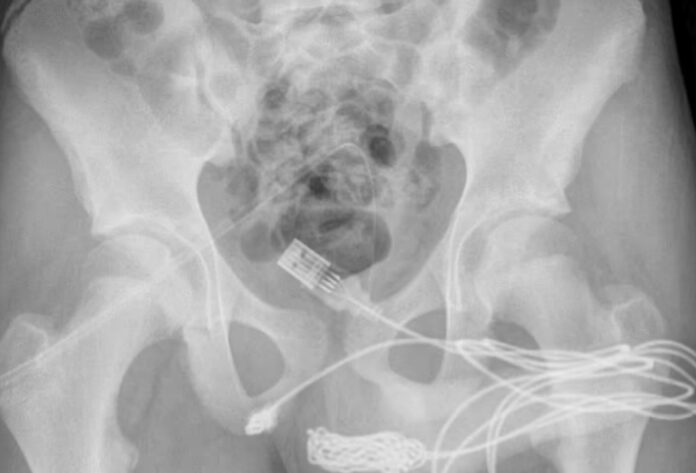

Ένα αρκετά περίεργο περιστατικό κλήθηκαν να αντιμετωπίσουν γιατροί στην Βρετανία καθώς ένας 15χρονος κατάφερε να σφηνώσει στο πέος του… ένα καλώδιο USB. Στην αρχή επιχείρησε να το αφαιρέσει μόνος του, αλλά – όπως ήταν αναμενόμενο – κατέληξε στο νοσοκομείο και υποβλήθηκε σε χειρουργείο.

Δυσκολία στην αφαίρεση του καλωδίου είχαν όμως και οι χειρούργοι του ουρολογικού τμήματος του νοσοκομείου. Αφού αφαιρέθηκαν τα βύσματα του USB, κατάφεραν τελικά να το αφαιρέσουν και μία μέρα αργότερα ο 15χρονος πήρε και εξιτήριο.